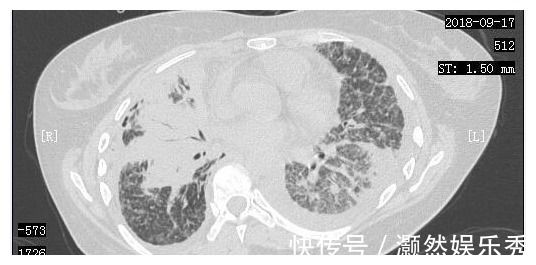

在经历了短暂的绝望后,小周一家决定齐心协力,积极进行抗癌治疗。2018年9月7日,小周进行了胸腔穿刺抽液,同时进行了胸腔灌注化疗。2018年9月14日,小周来到了我们医院进行治疗,复查了胸部CT,当时的胸部CT显示肺部一般情况非常差。